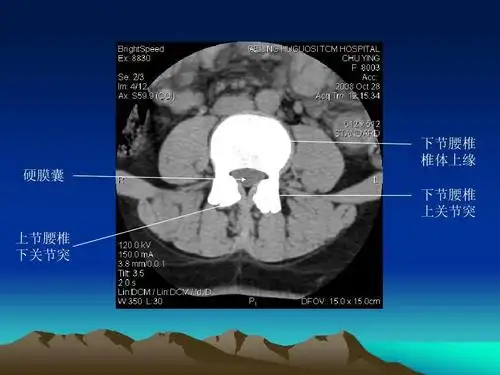

解剖学 断层解剖学 ppt 图7-2 经腰椎间盘和关节突关节的ct拖像

常规腰椎ct扫描层面:常规腰椎ct扫描l3-s1段,分为⑴椎体层面(骨窗)